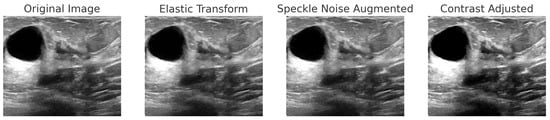

The INbreast dataset consists of 7632 full-field digital mammography (FFDM) images collected from 115 patients. Each image has been meticulously annotated by radiology experts to ensure high diagnostic accuracy. The dataset includes standard mammographic views—craniocaudal (CC) and mediolateral oblique (MLO)—for both breasts, although, in cases of mastectomy, only the remaining side is imaged. This dataset captures a variety of clinical scenarios, including screening, diagnostic, and follow-up procedures. For classification purposes, images are labeled as either benign or malignant. Benign cases encompass cysts, fibroadenomas, and calcifications, while malignant cases include tumors and suspicious lesions. What sets INbreast apart is its high-resolution imaging, acquired using a MammoNovation Siemens FFDM system with solid-state amorphous selenium detectors. The images are stored in DICOM format, featuring a resolution of 70 microns per pixel, with dimensions of either 3328 × 4084 or 2560 × 3328 pixels, depending on the compression plate used. Each image is accompanied by detailed XML-based annotations that provide information on lesion contours, types, biopsy results, and BI-RADS categories (3–6). Furthermore, the dataset includes patient metadata such as age, family history, BI-RADS assessments, and breast density classifications according to ACR standards. Figure 4 illustrates representative samples.